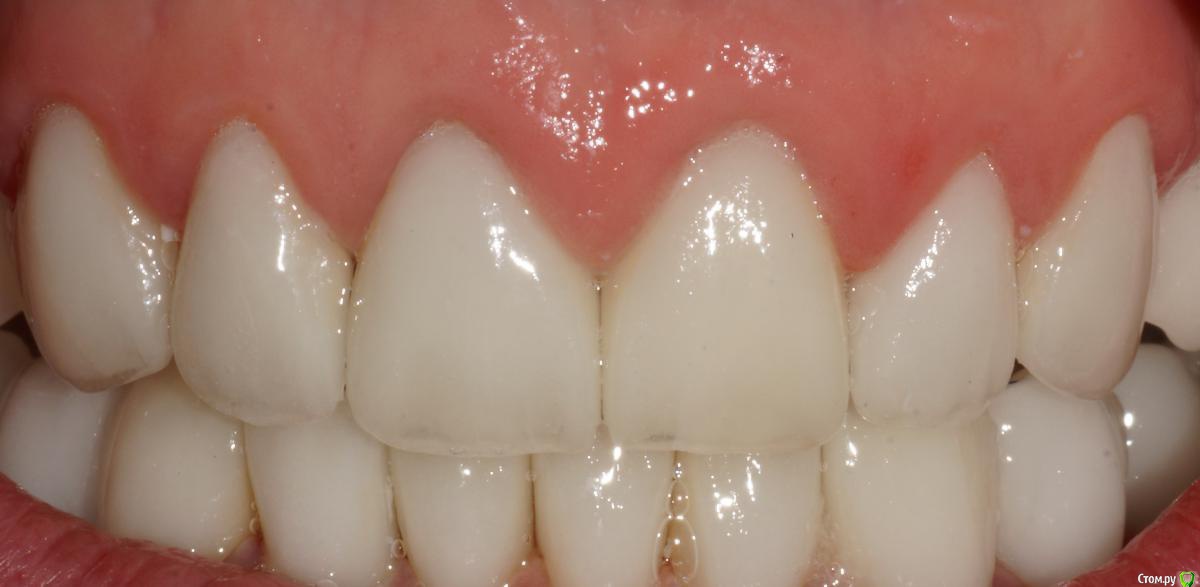

togrul Опубликовано 5 сентября, 2015 Автор Поделиться Опубликовано 5 сентября, 2015 Прошу прощение за качество фото. Ссылка на комментарий

Doc.IQ Опубликовано 6 сентября, 2015 Поделиться Опубликовано 6 сентября, 2015 Я так понимаю что кейс завершен..хотелось бы услышать приведенный в исполнение план..хоть и фото мало,но по не у видно,что работа очень хороша..покрайней мере фронт выглядит симпотно..Даже разные зениты двоек придают индивидуальности и живость..хотя некоторые и не согласятся со мной и скорее всего взяли бы в руки скальпель Ссылка на комментарий

togrul Опубликовано 6 сентября, 2015 Автор Поделиться Опубликовано 6 сентября, 2015 Я так понимаю что кейс завершен..хотелось бы услышать приведенный в исполнение план..хоть и фото мало,но по не у видно,что работа очень хороша..покрайней мере фронт выглядит симпотно..Даже разные зениты двоек придают индивидуальности и живость..хотя некоторые и не согласятся со мной и скорее всего взяли бы в руки скальпель Все верно кейс закончен)Мы согласовали вакс ап , перенесли в полость рта согласовали форму и размер передних зубов, не много переделали восковку. По силиконовым ключам отпрепарировали зубы и где то около 1,5 носили временные коронки и параллельно начали постоянную работу. Везде Емах одиночки, кроме 2 сегмента ,там поставили мост из 3 х ед. Место не было для имплантации + нужен был синус,подумали и решили сделать мост. Никакой хирургии не было только эндо.Фото будут Ссылка на комментарий